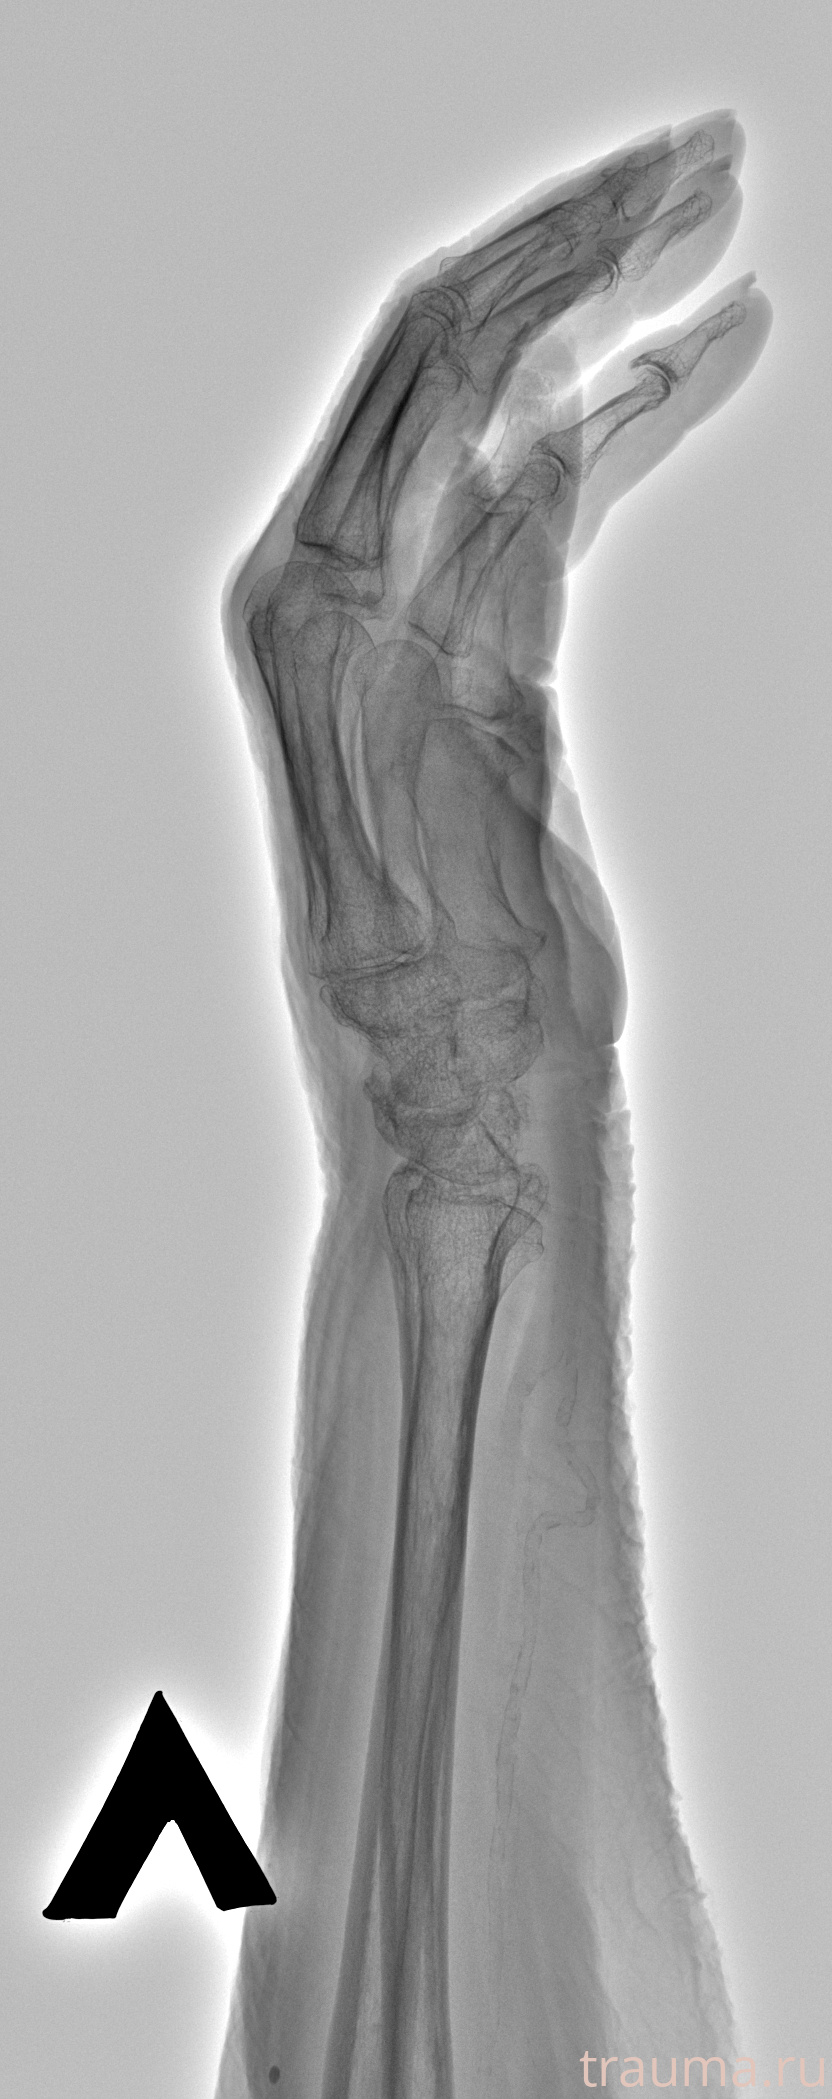

Рентген на дому: по вашему адресу приезжает врач-рентгенолог, травматолог-ортопед с мобильным рентгеновским аппаратом, проводит диагностику травмы или заболевания, делает необходимые рентгенограммы, дает рекомендации по дальнейшему лечению. Получить качественные снимки в домашних условиях возможно благодаря уникальной методике, разработанной МосРентген Центром для института  Склифосовского